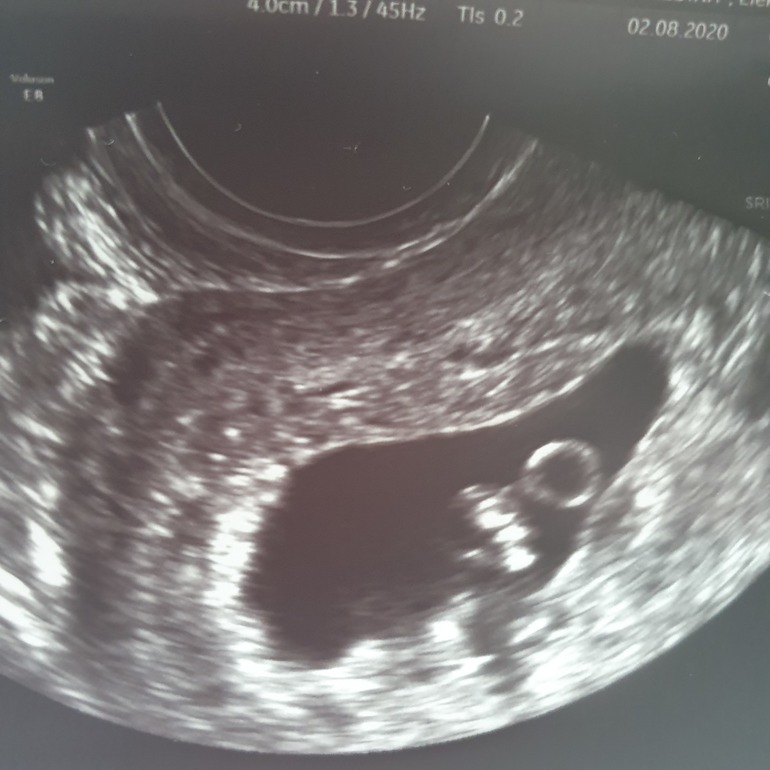

Диагноз ЗБ. Душа пуста😭

Вчера было по моим подсчётам, ровно 8 акушерских недель Беременности, решила проверить Сердечко и...никак не ожидала что такое может со мной произойти 😭

ЖМ отличный, плодное яйцо тоже,

Но не нашли никаких сосудиков у эмбриона...сказали замер на 6 неделе 🥺😭 мой малыш...😪 КТР 7мм.